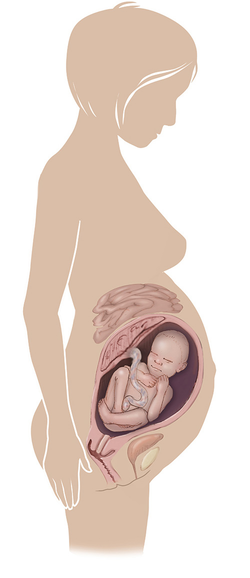

مراحل تطور الجنين أثناء الحمل

تطور الجنين خلال فترة الحمل على ثلاثة مراحل: أول 14 أسبوع من الحمل ، ثم تطوره بداية من الأسبوع 14 وحتى 28 أسبوعا ، ثم الثلث الأخير من 28 إلى 40 أسبوع من الحمل ... المزيد

مراحل تطور الحمل أسبوعيا بالصور

مراحل تطور الحمل أسبوعيا لكل من الأم والجنين داخل الرحم مدعومة بالصور التوضيحية ... المزيد